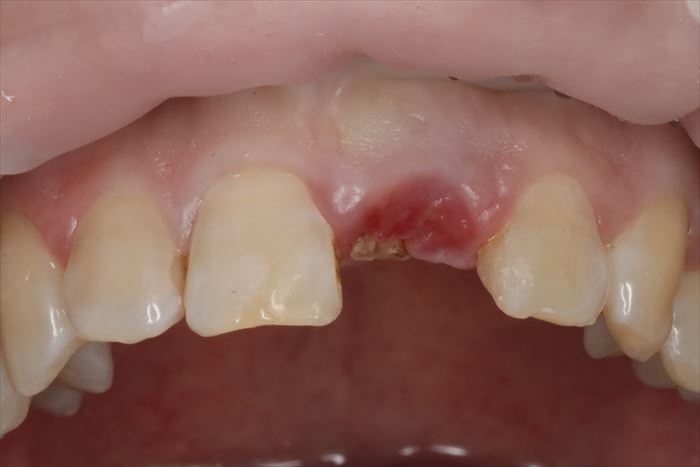

K・Tさんの初診時の上顎前歯の写真です。

左上中切歯(左上1:この歯は過去に神経を取ってある失活歯)の歯冠が折れて仮歯が接着してある状態です。

歯ぐき(歯肉)の表面に折れた歯根の一部が露出しています。